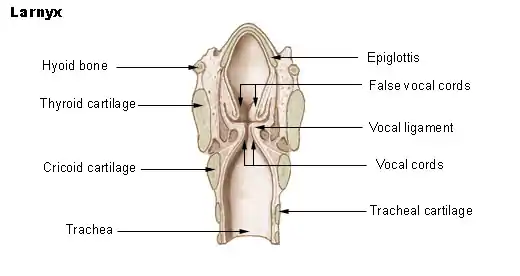

Additionally, LPR can cause inflammation in the vocal tract which results in the symptom of dysphonia or hoarseness. Hoarseness is considered to be one of the primary symptoms of LPR and is associated with complaints such as strain, vocal fatigue, musculoskeletal tension, and hard glottal attacks,[11] all of which can reduce a person's ability to communicate effectively.[12] Moreover, LPR patients may try to compensate for their hoarseness by increasing muscular tension in their vocal tract. This hyper-functional technique adopted in response to the inflammation caused by LPR can lead to a condition called muscle tension dysphonia and may persist even after the hoarseness and inflammation has disappeared. A speech–language pathologist will often need to be involved to help resolve this maladaptive, compensatory pattern through the implementation of voice therapy.[13]

LPR is often regarded as a subtype of GERD that occurs when stomach contents flow upward through the esophagus and reach the level of the larynx and pharynx. However, LPR is associated with a distinct presentation of symptoms.[10] LPR and GERD frequently differ in the relative prevalence of heartburn and throat clearing. While heartburn is present in over 80% of GERD cases, it occurs in only 20% of LPR cases. Throat clearing shows the opposite prevalence pattern, occurring in approximately 87% of LPR cases and in fewer than 5% of GERD cases.[8] Unlike GERD, LPR also poses a risk for bronchitis or pneumonitis as reflux of stomach acid to the level of the larynx can result in aspiration.[15] LPR is also commonly associated with erythema, or redness, as well as edema in the tissues of the larynx that are exposed to gastric contents.[10] In contrast, most cases of GERD are nonerosive, with no apparent injury to the mucosal lining of the esophageal tissue exposed to the refluxed material.[16]

Differences in the molecular structure of the epithelial tissue lining the laryngopharyngeal region may be partly responsible for the different symptomatic manifestations of LPR in comparison to GERD. In contrast to the resistant stratified squamous epithelium lining the esophagus, the larynx is lined by ciliated respiratory epithelium, which is more fragile and susceptible to damage. While the epithelium lining the esophagus is capable of withstanding as many as 50 instances of exposure to gastric contents each day, which is the uppermost estimate considered to be within the range of normal physiologic functioning, injury to laryngeal epithelium can occur following exposure to only small amounts of acidic gastric contents.[8]

Additionally, several potential biomarkers of LPR have been investigated. These include inflammatory cytokines, carbonic anyhydrase, E-cadherin and mucins; however, their direct implications in LPR are still being established.[22] The presence of pepsin, an enzyme produced in the stomach, in the hypopharynx has also become an increasingly researched biomarker for LPR.[23][24] Research suggests that the stomach enzyme pepsin plays a crucial role in the complex mechanism behind LPR.[25] Once present in the larynx pepsin is active at a low pH, but persists even when inactive.[26] Pepsin can manifest both extracellularly and intracellularly; however, damage is realized differently in these two environments.[26] Intracellularly, pepsin enters the laryngeal tissue through endocytosis and causes damage that accumulates over time.[26] Pepsin has implications on cellular transcription and therefore, gene expression, which subsequently leads to the recruitment of inflammatory cells, but inhibition of protective mechanisms such as growth factors.[26] Structurally, pepsin plays a role in increasing viscosity of the vibratory portion of the vocal folds and decreasing cellular water retention, which reduces the overall thickness of the vocal folds.[26] These morphological changes result in decreased vibratory amplitude, increasing demands for initiating vibration and ultimately, impacting voice quality.[26]